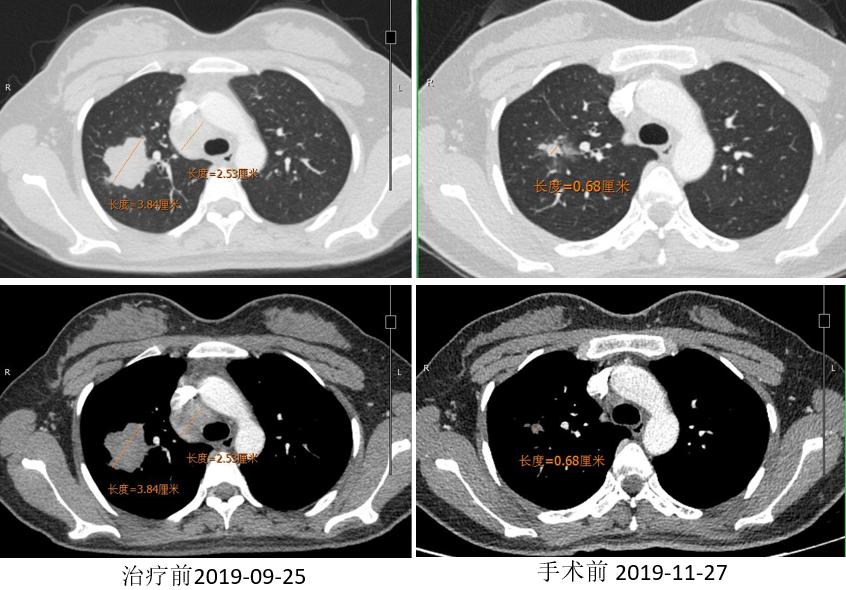

胸部CT

2019.12.10 行“右肺上叶切除术”。

术后病理:(右上叶)浸润性腺癌(腺管型95%,微乳头型5%),(纵隔4R组淋巴结)阴性。病灶内浸润性腺癌(约占20%),见较多区域纤维化伴组织细胞、淋巴细胞浸润,另见胆固醇结晶、多核巨细胞及肉芽肿反应,符合化疗后反应。